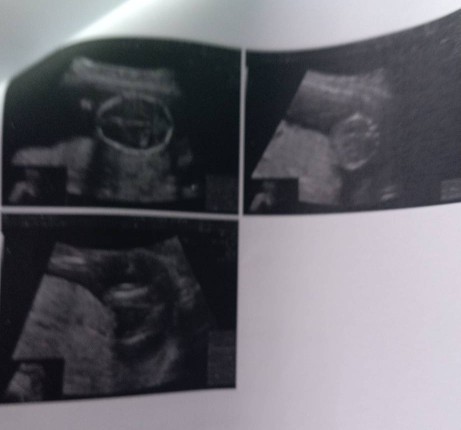

แม่ๆคะ ขอสอบถามคะ ภาพอัลตร้าซาวด์ แบบนี้คือปกติมั๊ยคะ 15 w +6

ไปตรวจคัดกรองอัลตราซาวด์ มาแล้วภาพซาวด์เป็นแบบนี้ รบกวนสอบถามแม่ๆคะ ว่าปกติใช่มั๊ยค่ะ หมอไม่ได้แจ้งหรือบอกอะไรเลยค่ะ

จริงๆหมอต้องเป็นคนชี้แจงด้วยค่ะ ตรงนี้ปกติไหม ตรงนี้มีปัญหาหรือเปล่า เพราะบางอย่างดูด้วยตาจากภาพซาวด์ไม่เห็นค่ะ ต้องดูต้องหมอซาวด์ บางทีถ้าหมอไม่ได้แจ้งอะไรก็แสดงว่าน้องปกติดีค่ะ ยังไงลองถามหมอดูนะคะ รอบหน้า